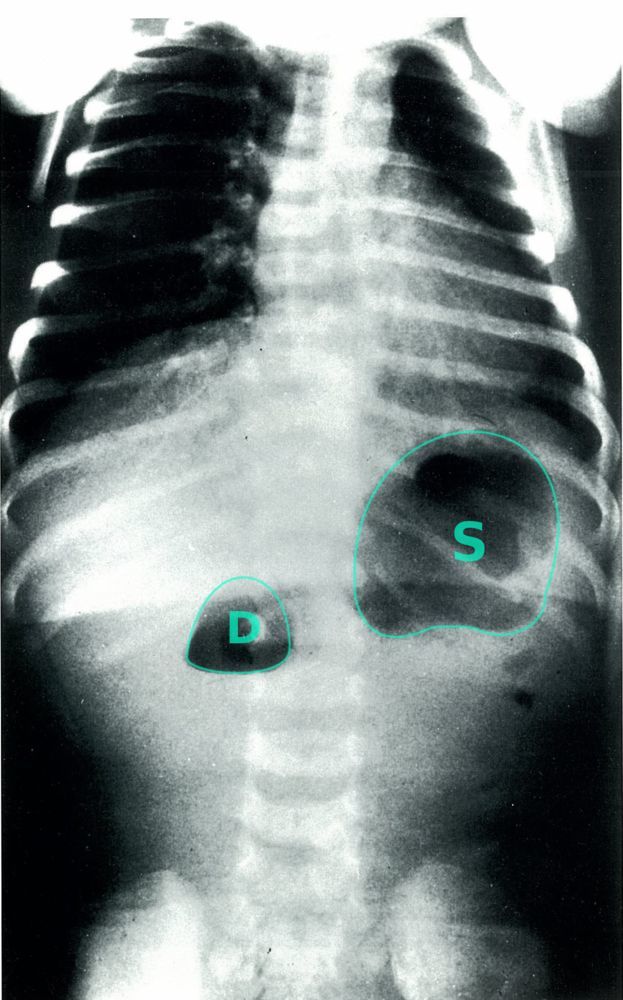

Double Bubble Sign on Ultrasound Seen in Duodenal Atresia

S → stomach

D → proximal duodenum

Shaded area → pyloric sphincter

Duodenal Atresia in a Newborn

(dilation of the pre-stenotic bowel segments (duodenum (D) and stomach (S)) with an air-fluid level in each dilated segment (double bubble sign). No air is visible in the post-stenotic bowel loops)